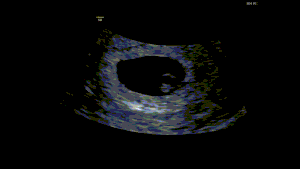

6-WEEK EARLY PREGNANCY SCAN

6 WEEKS

Looking for peace of mind earlier in your pregnancy? At Ultrascan, you can now book an early pregnancy scan from 6.5 weeks gestation. ….read more

EARLY PREGNANCY SCAN

8-14 WEEKS

Enjoy your pregnancy with peace of mind through our 2D ultrasound scans from as early as 8 weeks….read more